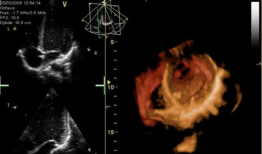

心脏跳动视频,揭秘心脏跳动的奥秘

你知道吗?最近在网上看到一个超级神奇的视频,简直让人心跳加速!就是那种心脏跳动的视频,感觉就像是在你的胸腔里亲自感受一样。今天,...